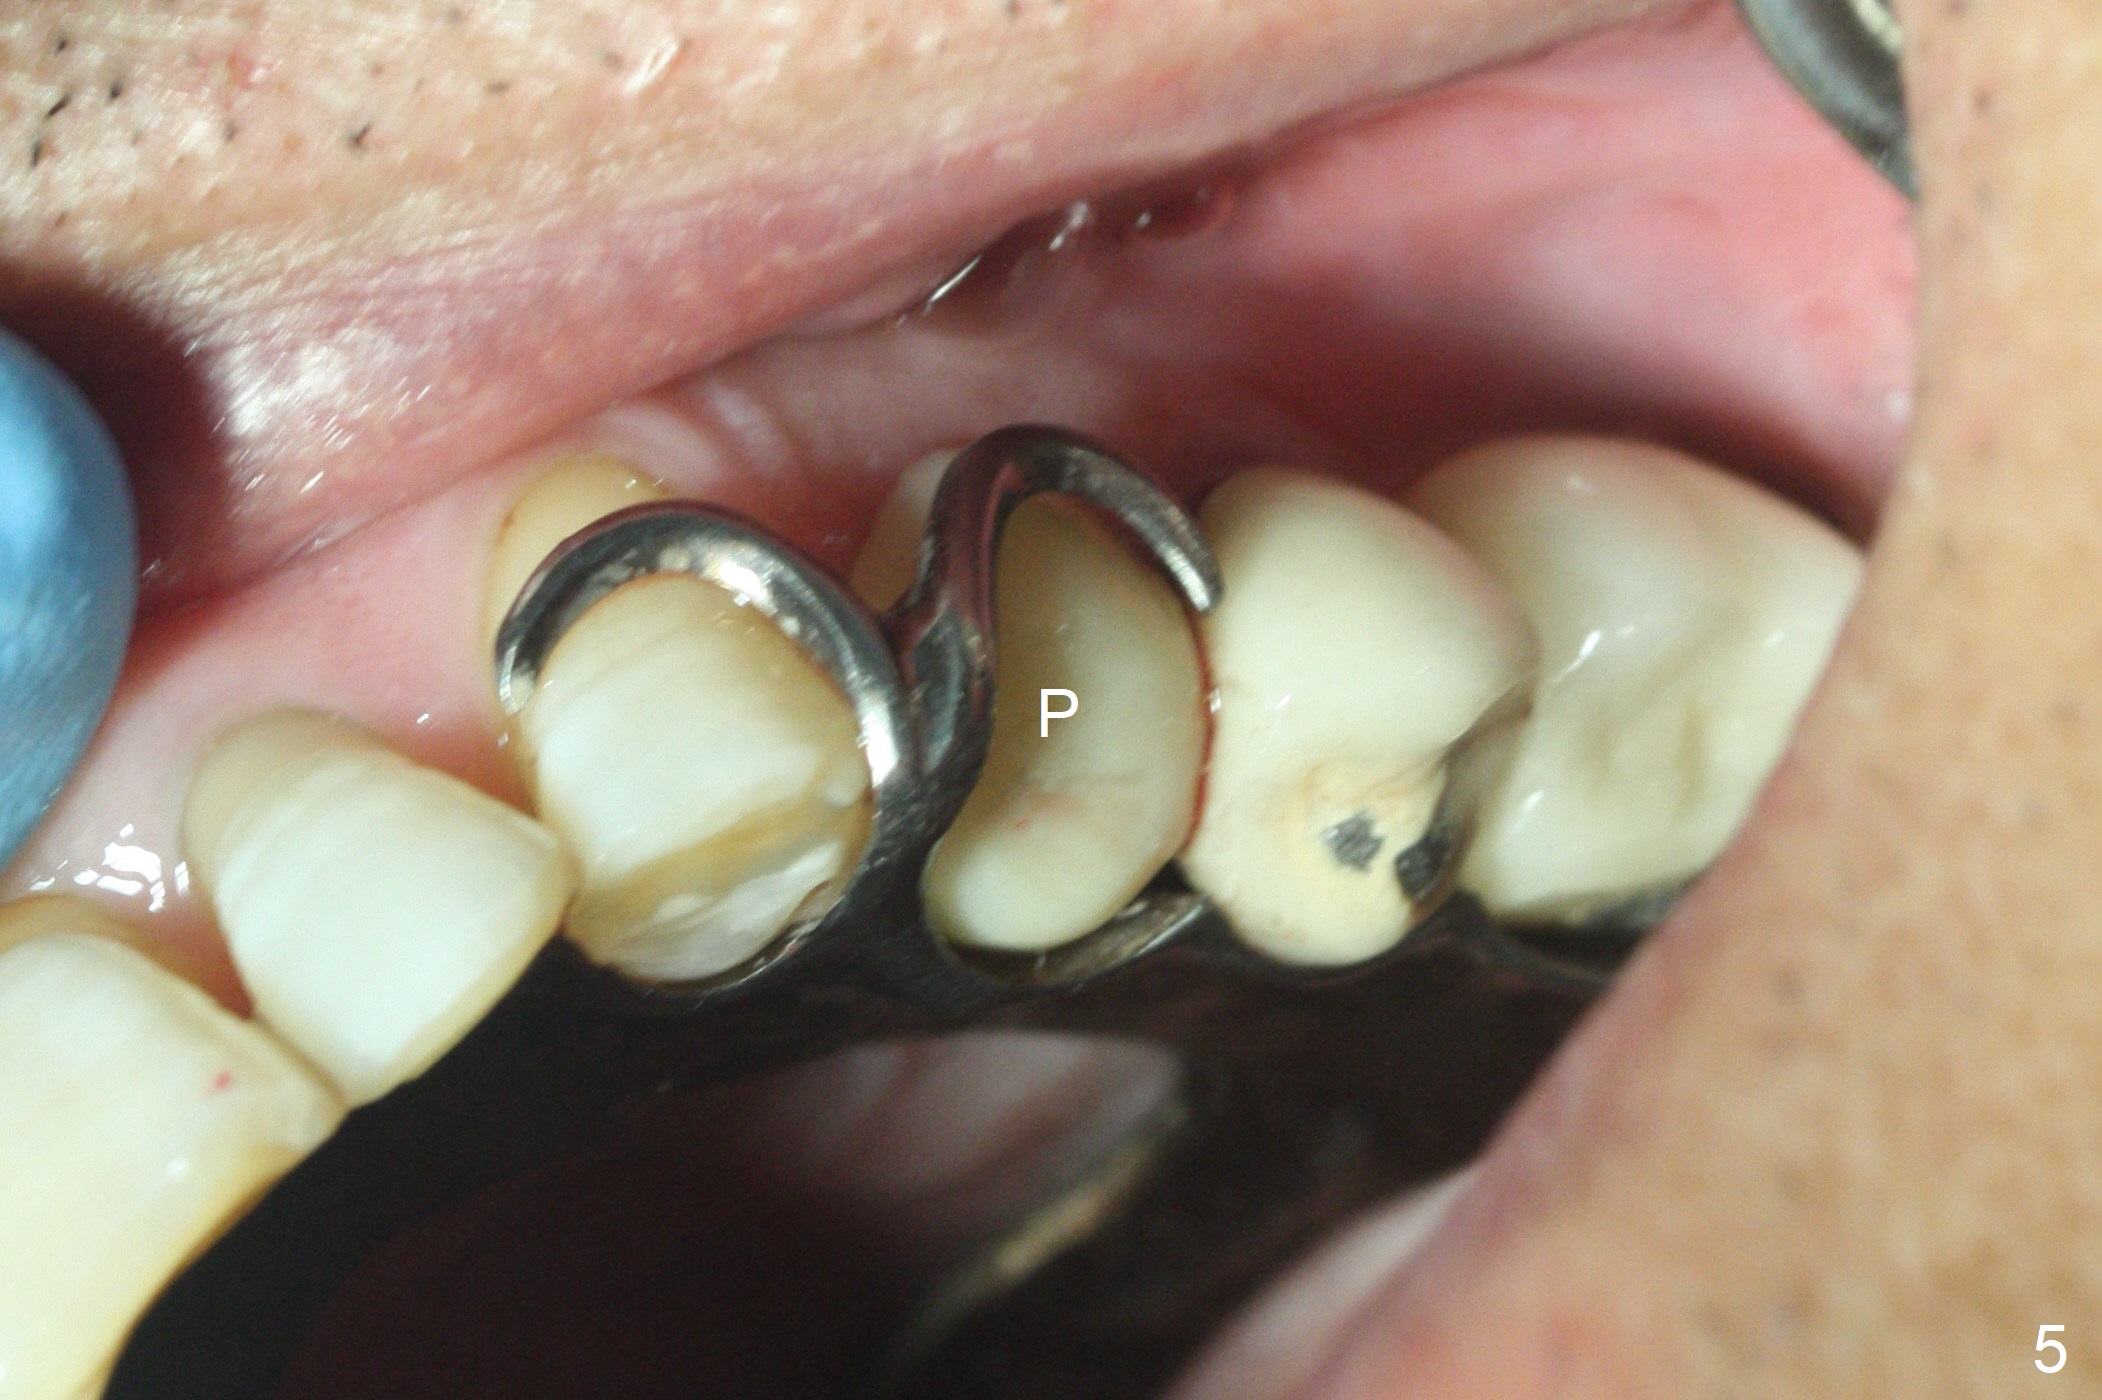

After extraction of the oval-shaped residual roots at #12 (Fig.1), osteotomy is initiated in the palatal socket for 18 mm; since the root of the canine curves distal (Fig.2 red dashed line), the osteotomy cannot afford to move mesial and extend more apical. A 3.8x15 mm implant is placed with > 50 Ncm (Fig.3). With immediate placement of a 4.5x4(3) mm abutment, an immediate provisional is fabricated to close the sockets (Fig.4 P). The provisional has clearance from the RPD clasps (Fig.5). In fact the implant could be longer, as shown by immediately postop panoramic X-ray (Fig.6). The implant seems to be osteointegrated 3 months postop (Fig.7). The tooth #13 is symptomatic with caries (Fig.8 C) 7 months post #12 crown cementation; the #13-15 FPD dislodges. The upper left quadrant is cold and hot sensitive 2.5 months post RCT (Fig.9); although there is mild percussion at #13, pulpal test shows that the tooth #15 has lingering pain. The FPD was recemented temporarily after RCT; it cannot be removed. The implant crown has been loose for several months during the pandemic before he returns 2 years 7 months post cementation. In fact the abutment has been not seated completely (from Fig.3 to 9). The crown/abutment is removed from the mouth; the crown is sectioned and separated from the abutment; the latter is reseated, but incompletely (Fig.10 <). With suspicion of the mesial crestal contact, profile drills 4.6 and 5.5 mm are used without effect. A new (old probably being worn) and longer (easy to turn in the narrow space) abutment is finally seated completely (Fig.11 (no gap)). After occlusal adjustment, abutment level impression is taken for a new crown.